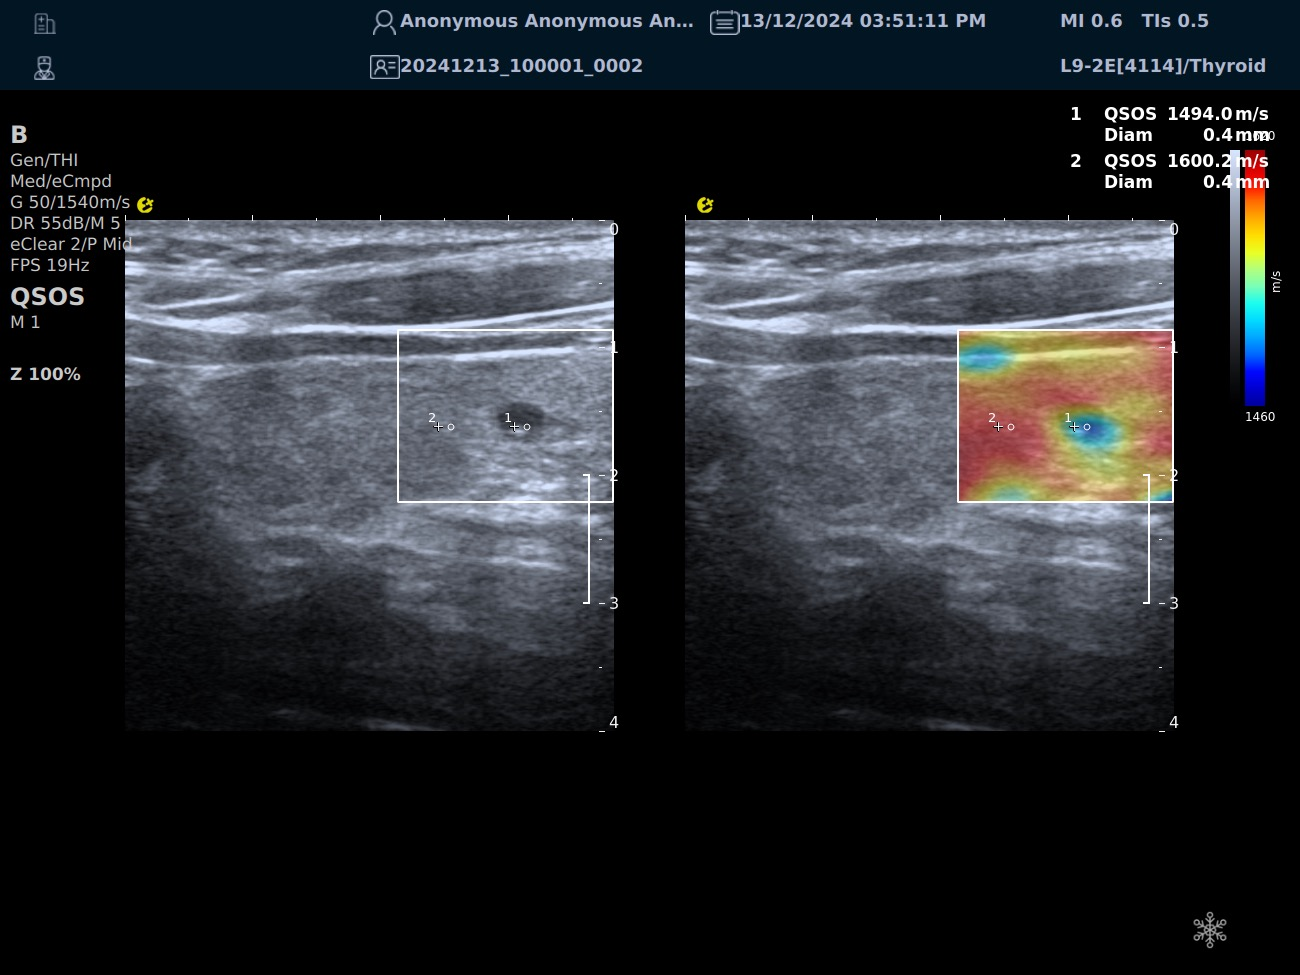

QSOS声速定量成像

QSOS声速成像技术利用声波在组织中的传播速度差异性,计算不同位置的声速值,反映组织的物理特性。

利用超声探头发射超声波脉冲,分析反射信号的时间延迟,确定声波传播路径和速度,构建声速分布图像。

图像显示

QSOS技术采用彩色编码显示声速图像,不同颜色代表不同声速值,便于医生识别病变部位和测量。

25fb8cb17586b86e5d915a2be3025a2.png

技术优势

?精准定量反映组织特性,成像更敏锐?彩色编码直观显示,轻松发现异常?捕捉声速差异,早期、微小病变更易察觉

肌骨领域的应用

?精准定位损伤部位?判断损伤严重程度?监测肌肉营养?评估肌少症?骨质疏松评估